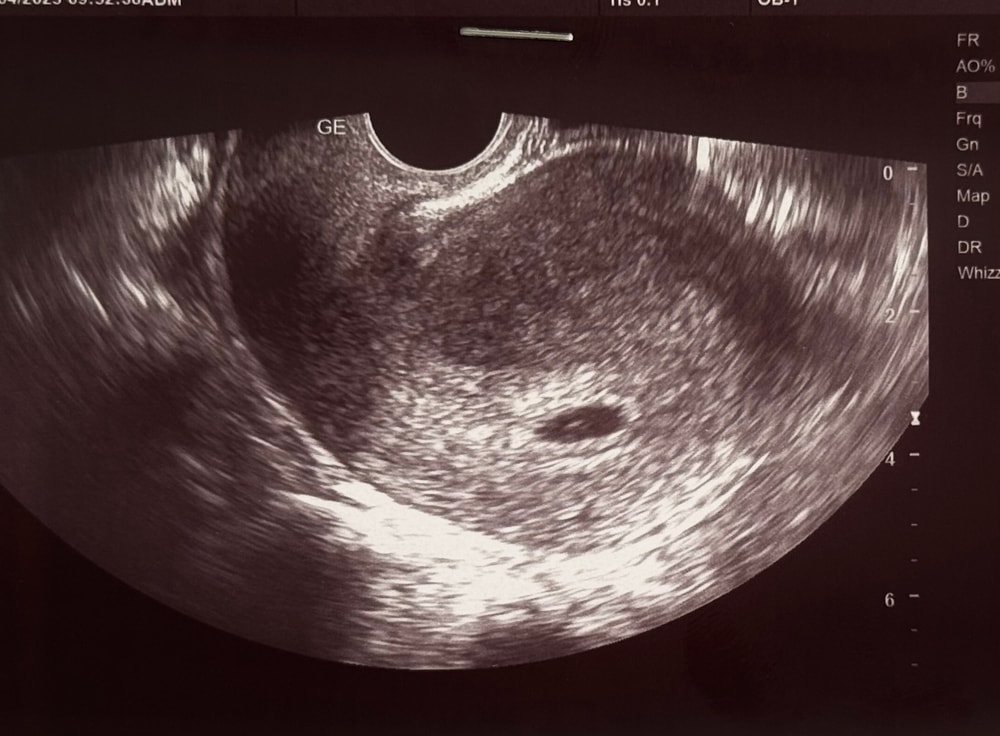

Сравнила УЗИ:

1 беременность 18дпо: 02.03 пя 0,22мм

13.03 пя 5+2 4,7мм

21.03 пя 6+4 7,6 мм

27.03 пя 7+3 11,9 мм

не нашли за это время жм и эмбриона - вакуум

2 беременность 17дпо 15.04 пя 4+5 - 3,2мм

24дпо 21.04 пя 5+4 - 10,3мм + жм 2,2мм❤️